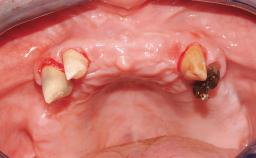

Immediate Loading of Eight Implants in the Maxilla and Six Implants in the Mandible and Final Restoration with Three-Unit and Four-Unit FDPs

Extensive scientific evidence has confirmed that immediately loaded implants with fixed full-arch provisional restorations can osseointegrate with success rates similar to conventionally or delayed loaded implants. A number of immediate-provisionalization techniques for edentulous jaws have been described. Some protocols differ when it comes to prefabricated provisional templates versus complete denture conversion; intrasurgical impressions versus direct relining; and cemented versus screw-retained provisional restorations. In this context, complete-denture conversion has been proposed for either intrasurgical impressions or direct relining. Another possibility is the utilization of a prefabricated provisional to be adapted either in the mouth (by direct relining) or in the laboratory (on a working model obtained from an intrasurgical impression).

Case Type Edentulous Maxilla

Jaw Maxilla and Mandible

Defining Characteristics Fully edentulous upper jaw to be rehabilitated with four or more implants